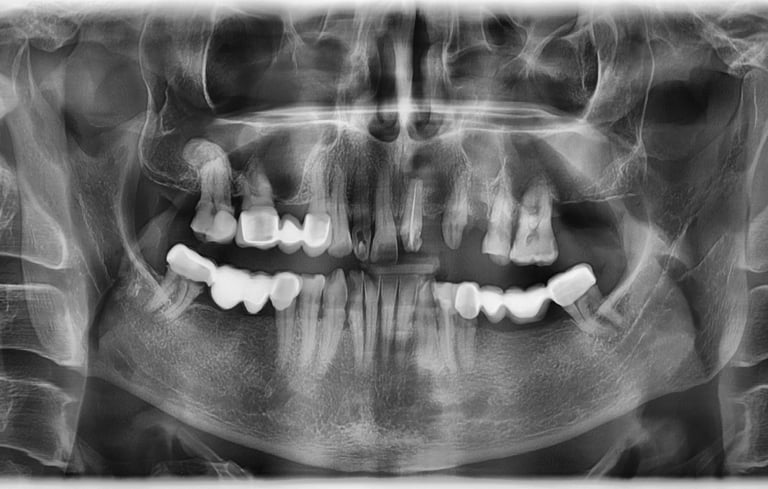

Reabilitare implantara in cazul unor dinti restanti irecuperabili, cu mobilitate severa. Dupa extractia atraumatica a dintilor compromisi, tratamentul continua cu inserarea implanturilor dentare. In prealabil, in urma cu 6 luni s-a realizat aditie osoasa prin sinus lift extern la nivelul cadranului II, tehnica chirurgicala care ne-a permis inserarea implanturile posterioare.